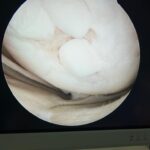

a) Inestabilidad fémoro-rotuliana: freecuente en mujeres jóvenes, deportistas, hiperelásticas y con escasa musculatura cuadricipital. Generalmente se soluciona con tratamiento rehabilitador, pero en casos recidivantes puede ser necesario recurrir a la cirugía, como muestra el caso de lasfotos que se muestran a la derecha, que representan a un deportista que sufrió varias luxaciones de rótula (desplazamiento fuera de su sitio anatómico) que requirió cirugía artroscópica donde se evidenció daño del cartílago de la rótula.